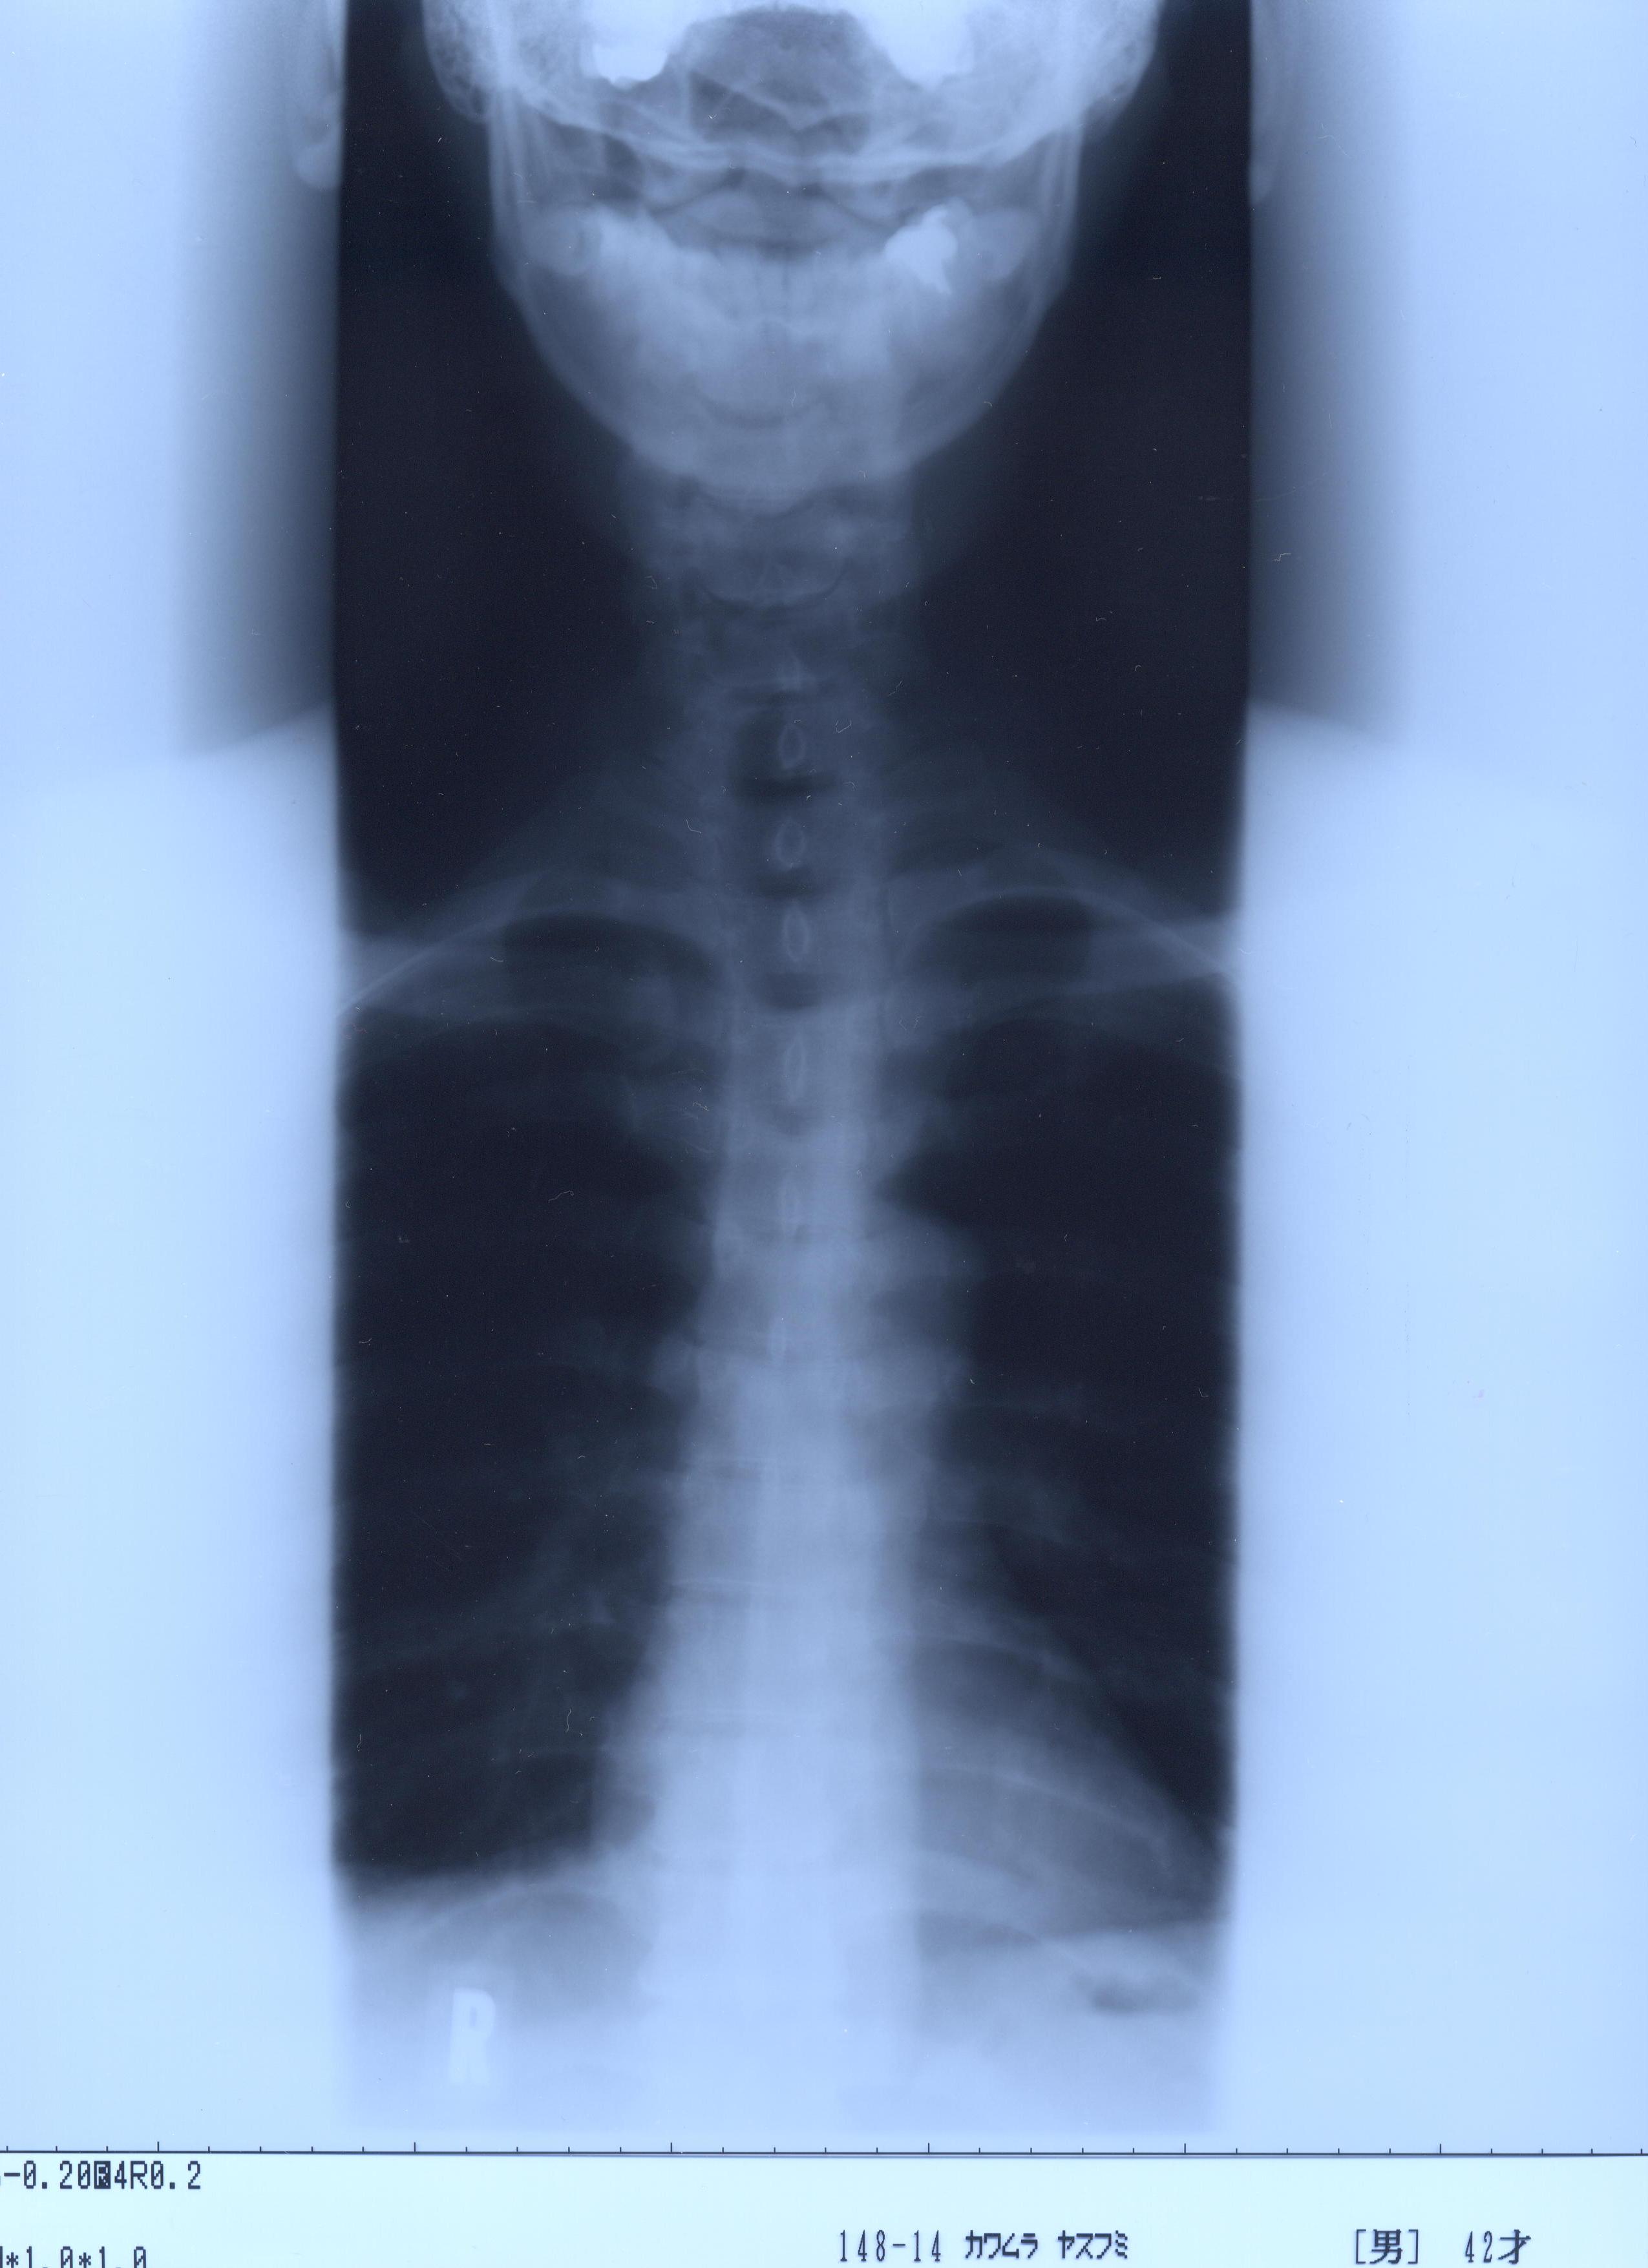

@@Ž„‚Μ”wœ‚Μ‚wόŽΚ^‚Ε‚·@@˜‚ͺ’Ι‚­‚Δ’Ι‚­‚āII@2002/1/22ŽB‰e

‚SDŽρ‚̐³–ʁ@@Šg‘ε